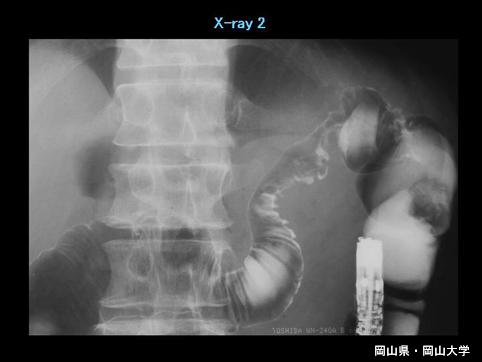

Disentería Amebiana de Intestino Grueso, que muestra evidente estenosis en el colon transverso

Enfermedad Inflamatoria - Ulcerativa/Disentería Amebiana

colon/transverso

Rayos X

40 -